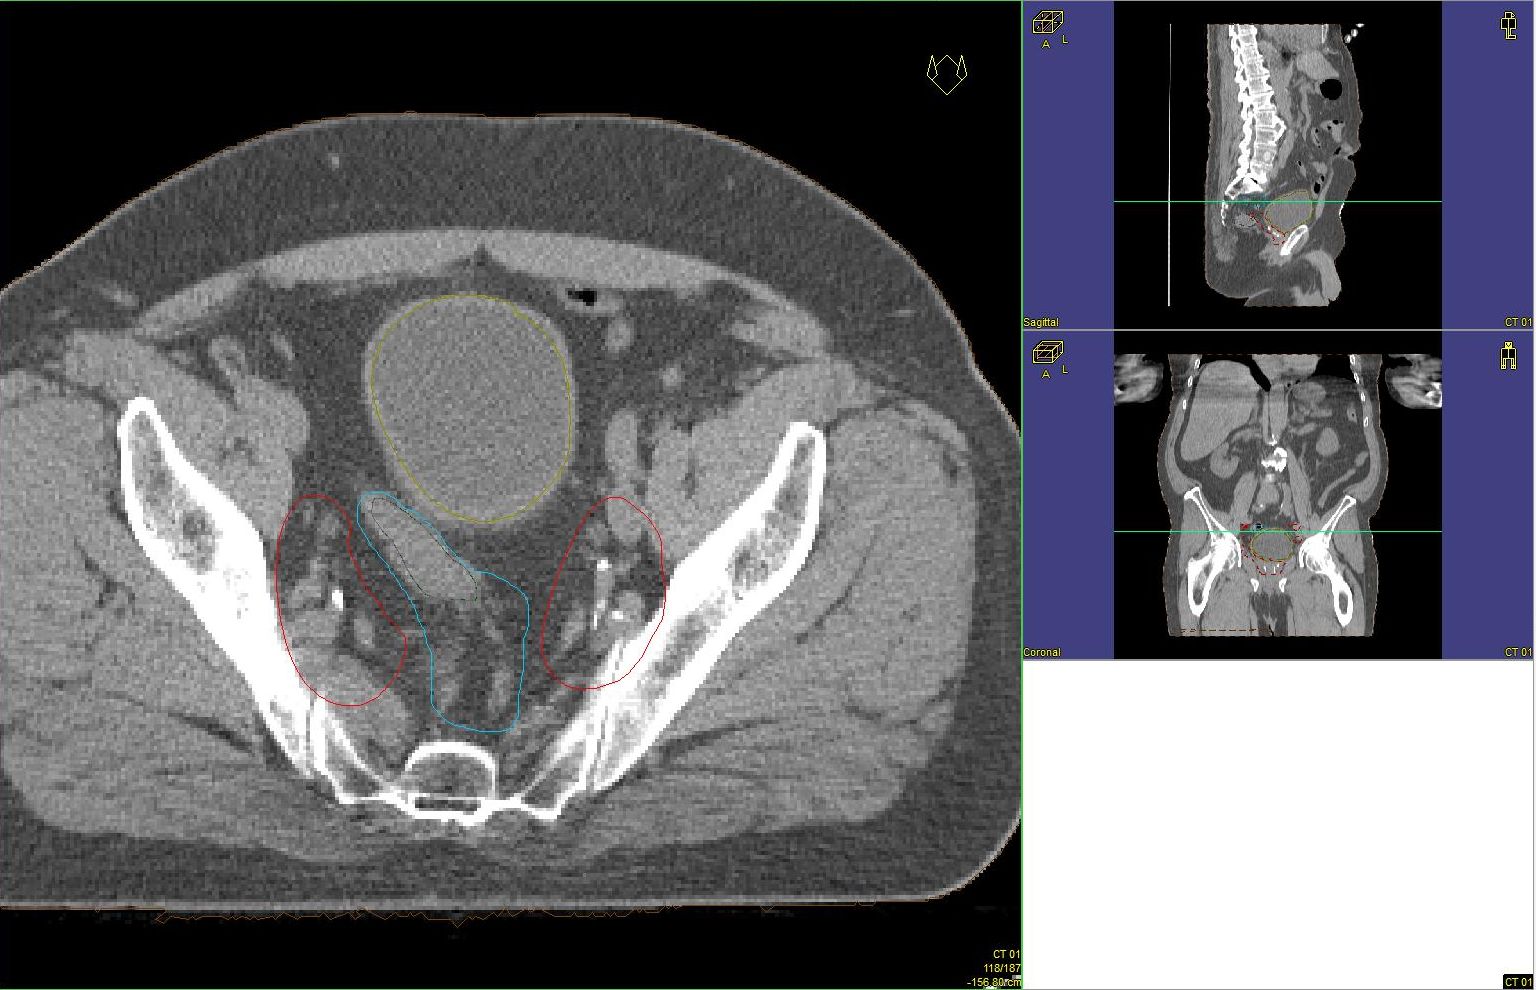

Prostata-Ca: Zielvolumen der postoperativen Radiotherapie

Beispiel: postoperative RT